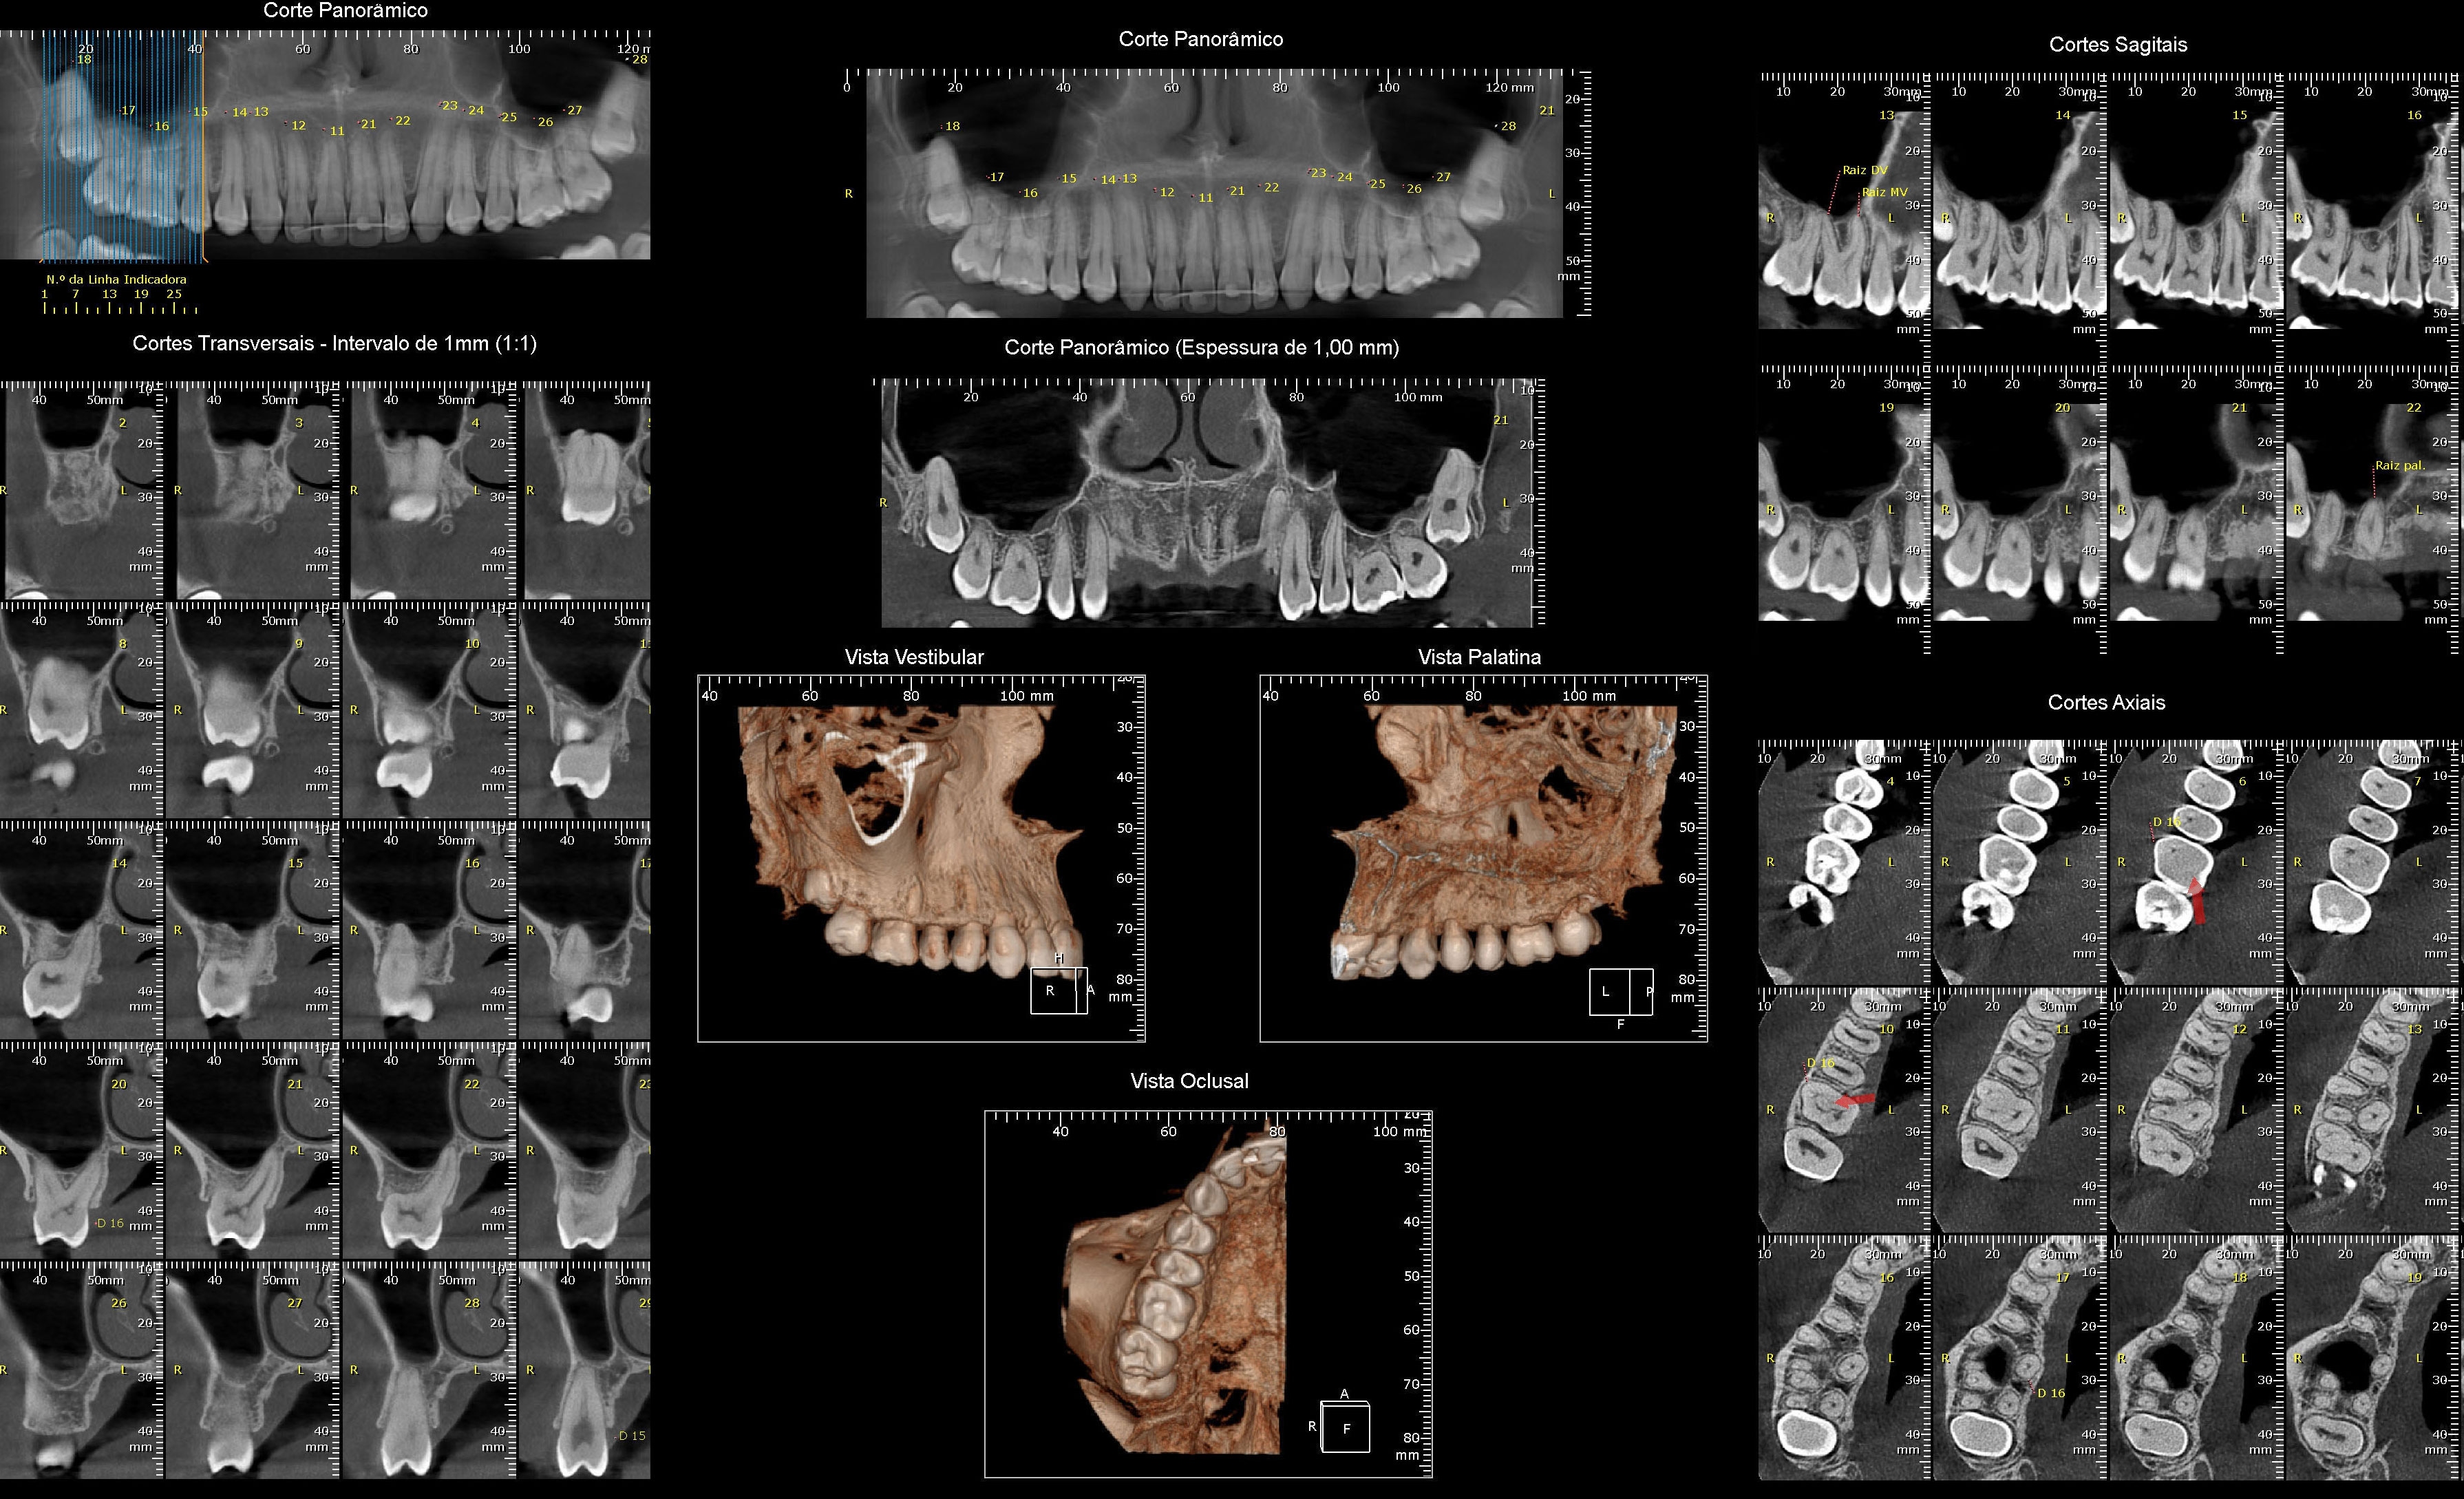

Tomografia Computadorizada

- Exame Tridimensional

- Tomógrafo de Altíssima Resolução